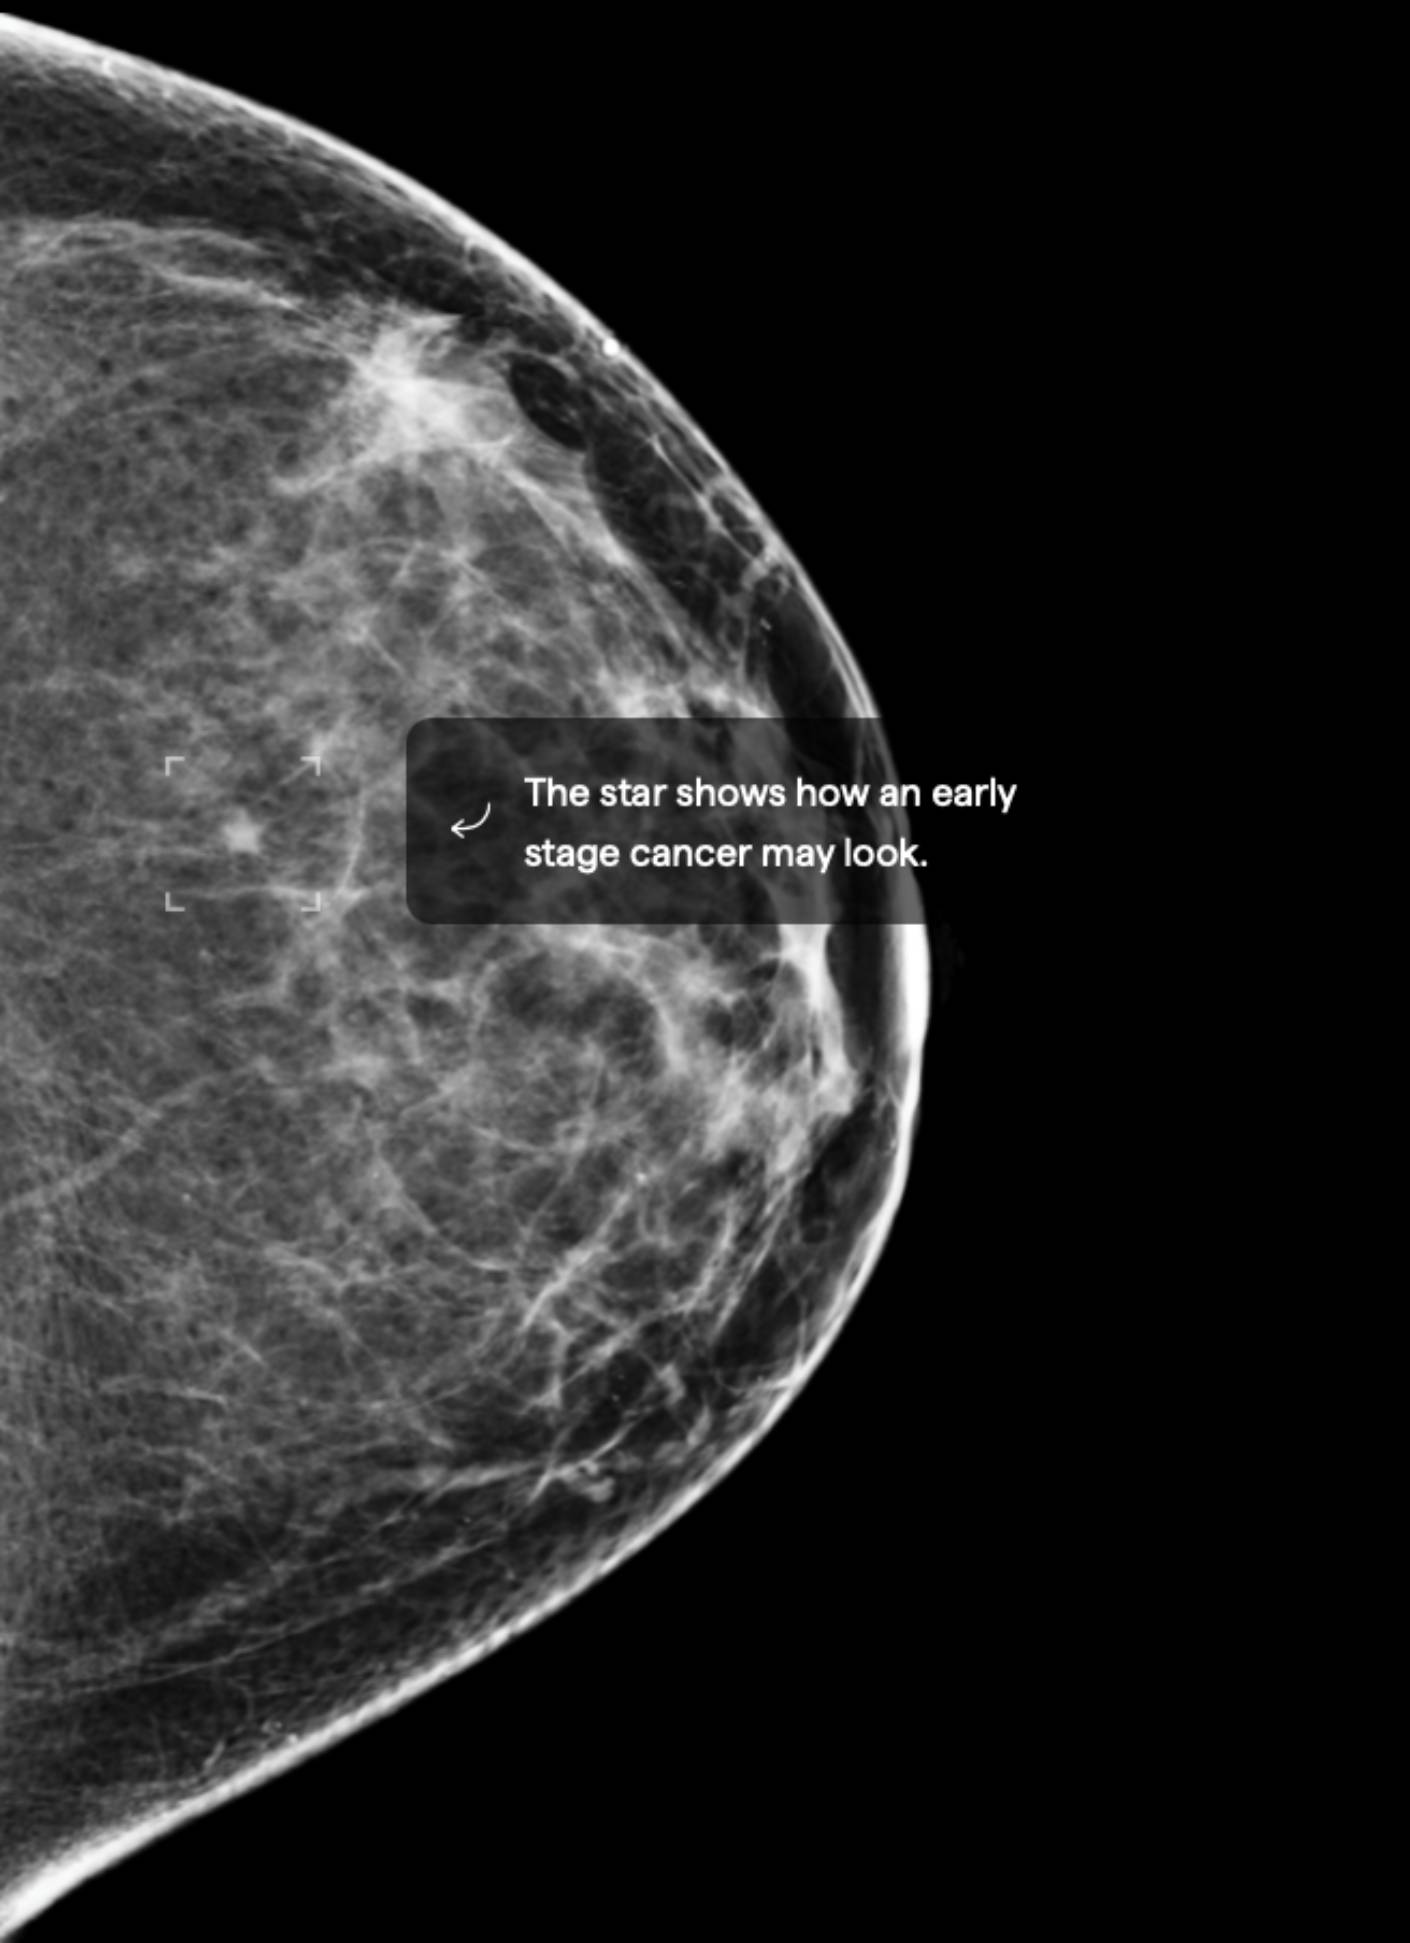

7.5% Mammographic Density

About 40% of female breasts fit category “C”. They are referred to as “heterogeneously dense breasts”.1

Your dense tissue could hide masses on your mammogram.3 Consider asking your doctor if additional ultrasound or MRI imaging should become part of your screening schedule. Also consider asking about a risk assessment to help both of you better understand your lifetime risk for breast cancer.